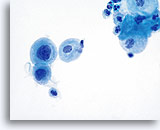

Postpartum Changes

During the postpartum period, or if breast feeding, a hormonal pattern of low squamous maturation predominates. Parabasal cells are abundant, usually presenting singly. Glycogen may also be present. A background of inflammatory cells and reactive changes is often present and may require additional scrutiny. Adherence to strict cytologic criteria (the lack of an increased N/C ratio, abnormal chromatin and irregular nuclear membranes) should preclude an over-diagnosis of cytologic atypia.

Postpartum

High power view of parabasal cells during postpartum. Note presence of glycogen and low N/C ratio. 60X